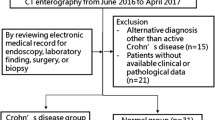

This retrospective study was approved by the instutional ethics committee and the requirement for informed consent was waived. CTE scans that were obtained between June 2016 and September 2017 in patients with known or suspected CD were reviewed.

Inclusion criteria were as follows: (a) adult patients (> 18 years old), (b) patients who underwent dual-energy CTE due to suspected CD, (c) patients who had clinical, laboratory, and histopathological data at the time of CTE including time interval 1 month after the scan.

All patients with imaging findings of CD that were identified on CTE underwent ileocolonoscopy. The electronic medical records of patients regarding findings of ileocolonoscopy, operation, histopathology, and laboratory were reviewed.

Of the 68 adult patients who were identified, 5 who did not have available clinical or pathological data and 2 who had an alternative diagnosis other than CD were excluded. The study included a total of 61 patients with and without CD. 47 patients (24 men and 23 women; median age 46 years, range 22–75 years) were diagnosed as having active CD on CTE and the affected bowel walls seen on CT were confirmed by ileocolonoscopy. Of 47 patients with CD, 11 underwent surgery. The remaining 14 patients (7 men and 7 women; median age 35.5 years, range 24–79 years) who underwent CTE due to suspected CD, had a negative diagnosis of CD with no specific finding of bowel disease.